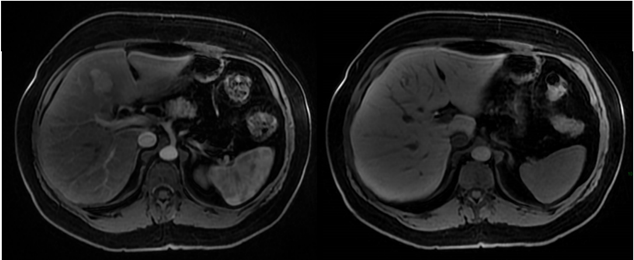

Mulher de 45 anos, sem história pessoal de câncer, foi submetida a exame de ressonância magnética do abdome superior com contraste venoso hepatoespecífico após achado de nódulo hepático incidental em ultrassonografia. Nas sequências pré-contraste, o nódulo apresentava discreto baixo sinal na ponderação T1 e discreto alto sinal na ponderação T2, ambas com supressão de gordura. Abaixo temos imagens nas sequências T1 em fase, T1 fora de fase, T1 pós-contraste (fase arterial) e T1 pós-contraste (fase hepatobiliar). As sequências pós-contraste mostram que o nódulo apresenta intenso realce arterial e hipossinal em relação ao parênquima na fase hepatobiliar.

Diante do exposto acima, analise as afirmativas abaixo e assinale a alternativa correta.

I. Há queda de sinal na ponderação T1 fora de fase tanto no parênquima hepático como no nódulo do segmento IV hepático em relação à ponderação T1 em fase, sugerindo quantidade significativa de gordura intracelular no parênquima e no nódulo.

II. O nódulo do segmento IV hepático tem características compatíveis com hiperplasia nodular focal.

III. O nódulo do segmento IV hepático tem características compatíveis com adenoma esteatótico.

IV. O meio de contraste hepatoespecífico auxilia no diagnóstico diferencial entre hiperplasia nodular focal e adenoma, uma vez que a hiperplasia nodular focal não capta contraste significativamente ou exibe apenas halo captante na fase hepatobiliar, enquanto o adenoma apresenta realce igual ou maior que o do parênquima hepático na mesma fase.